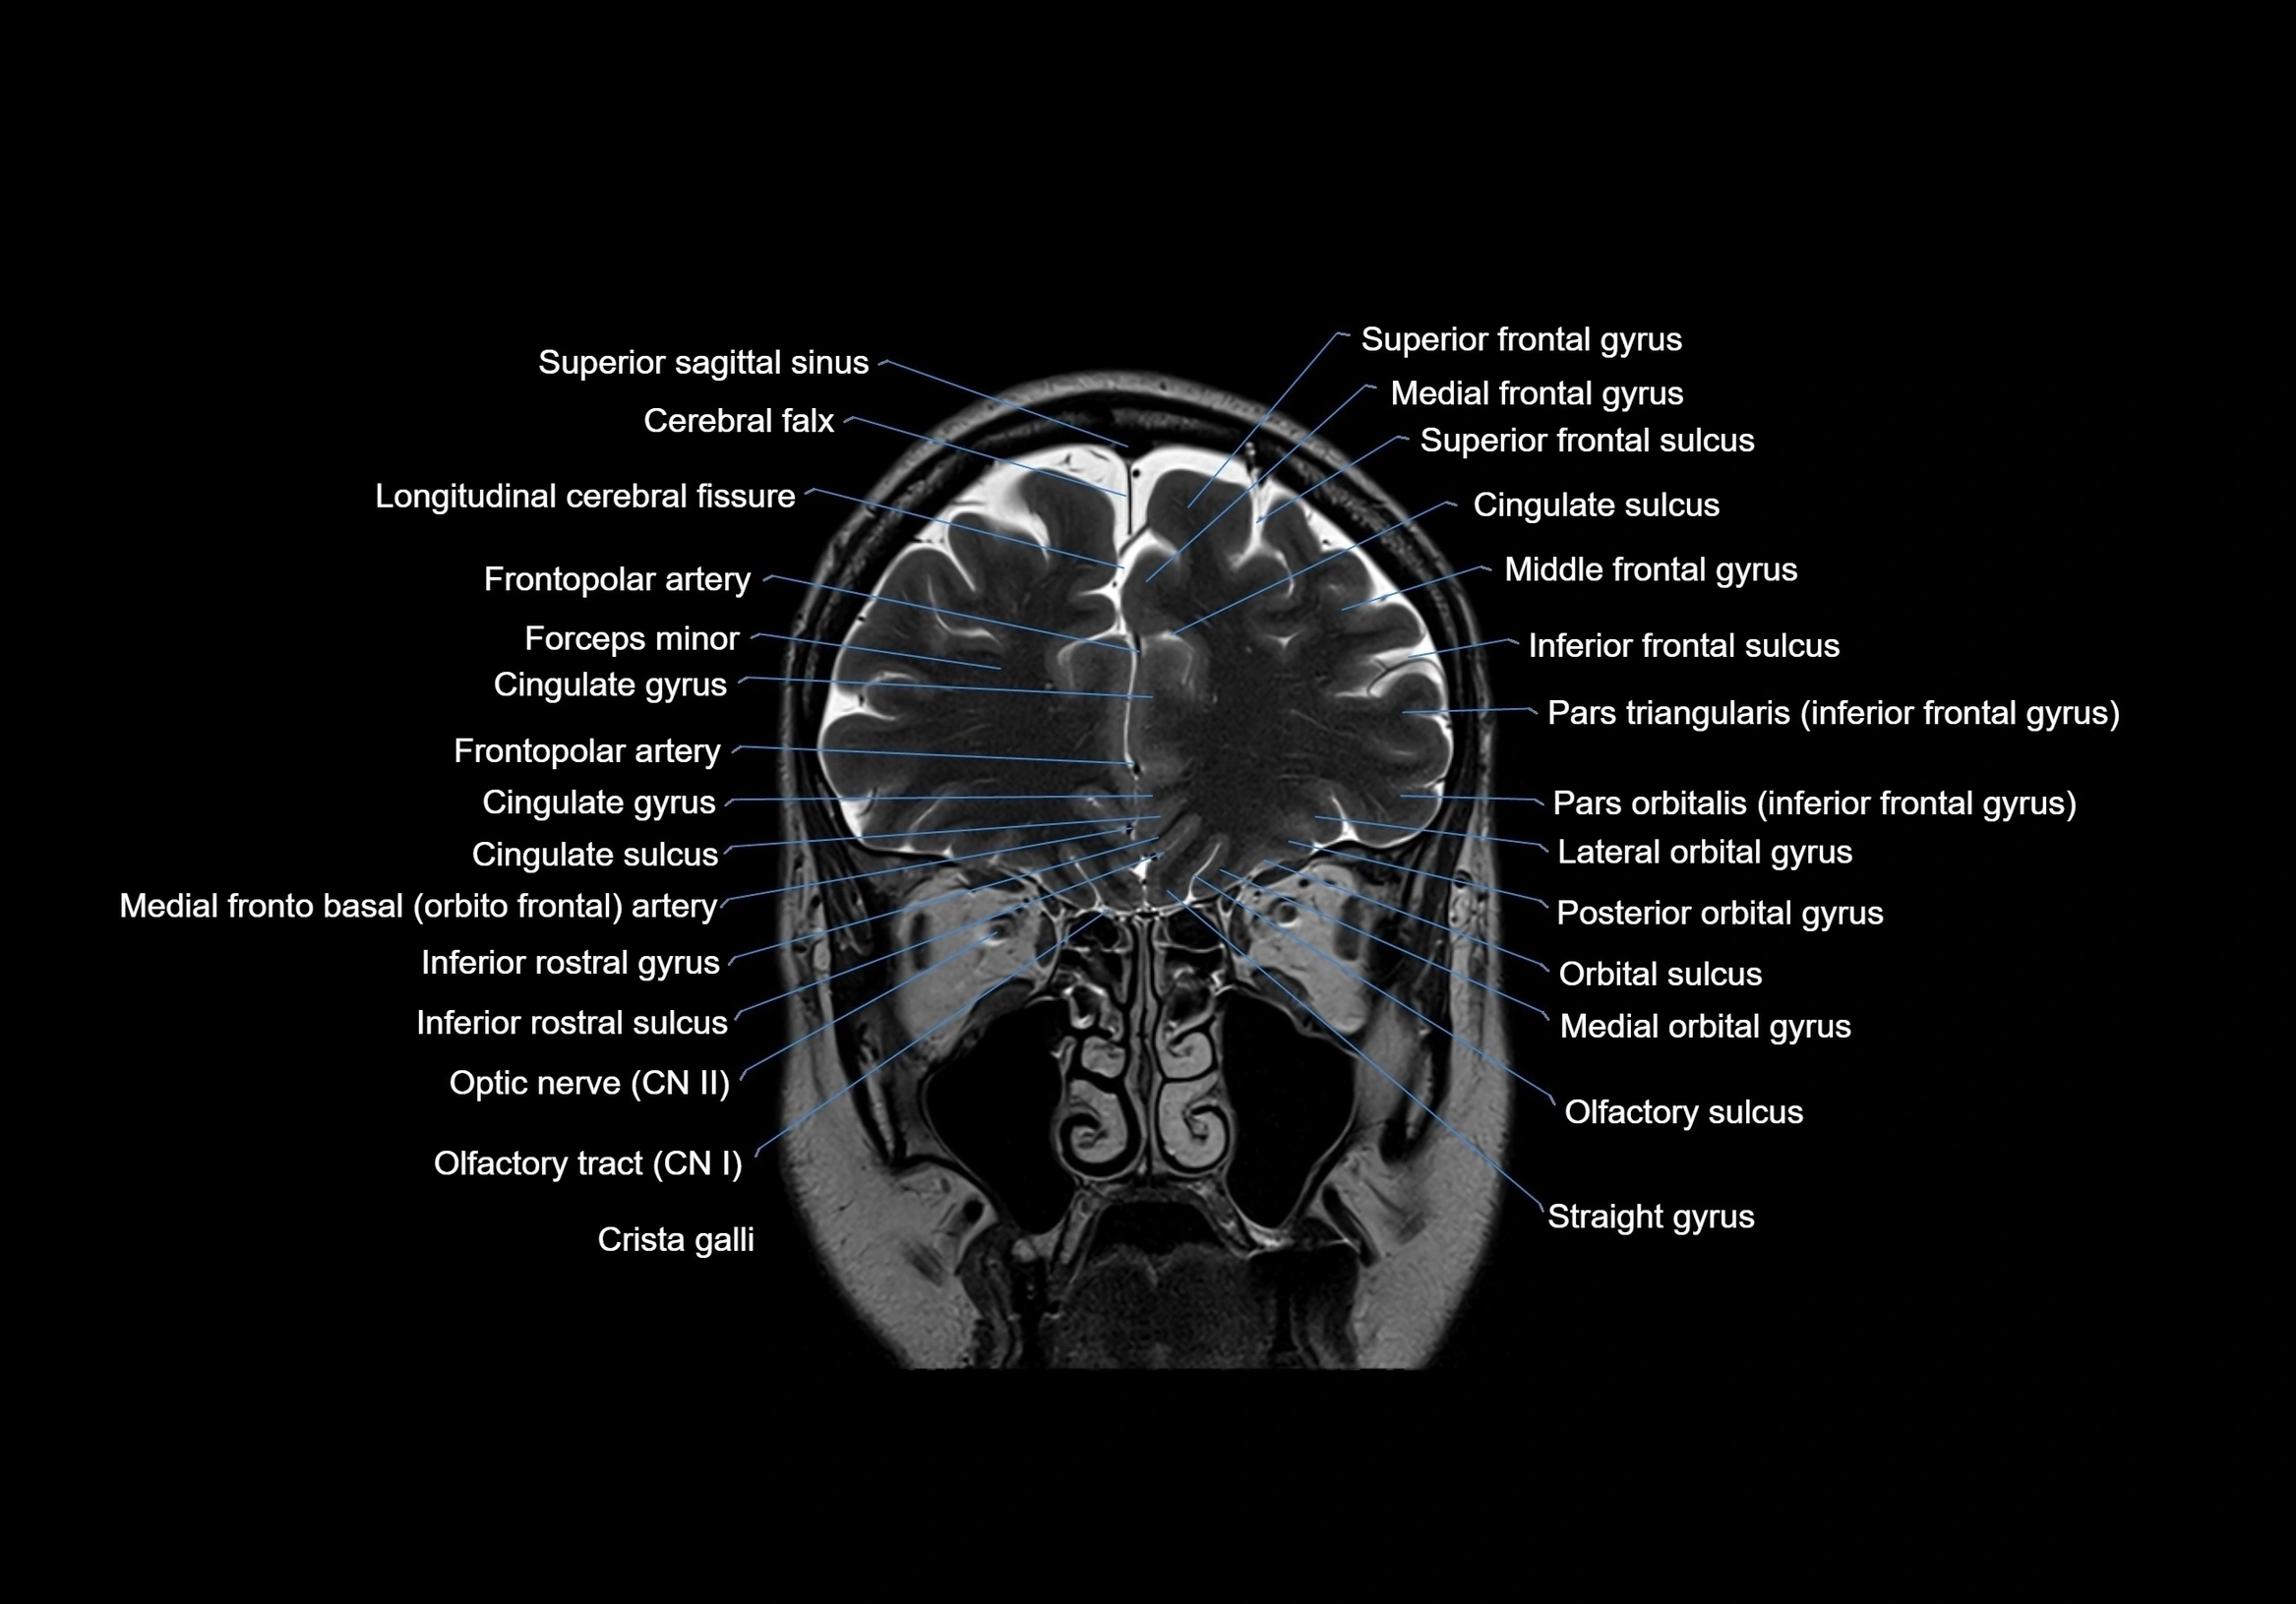

- Cerebral falx

- Cingulate gyrus

- Cingulate sulcus

- Crista galli

- Frontopolar artery

- Inferior frontal gyrus

- Inferior frontal sulcus

- Lateral orbital gyrus

- Longitudinal cerebral fissure

- Medial frontal gyrus

- Medial frontobasal artery

- Medial orbital gyrus

- Middle frontal gyrus

- Olfactory sulcus

- Olfactory tract

- Optic Nerve (Cranial Nerve II)

- Pars orbitalis of inferior frontal gyrus

- Pars triangularis of inferior frontal gyrus

- Straight gyrus

- Superior frontal gyrus

- Superior frontal sulcus

- Superior sagittal sinus